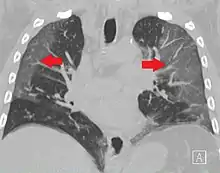

CT image showing ground-glass opacification in the posterior of the right lung (screen left). - Measles

CT image showing diffuse GGOs throughout both lungs. An abscess is also noted in the right lung (screen left). - Adenocarcinoma in situ of the lung